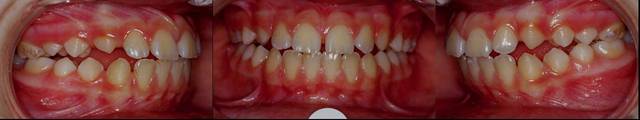

Suite et fin, photos

Bipro fin  exo hrewbh - Eugenol

Bipro avant apres ppqeoj - Eugenol

beau travail d’interception